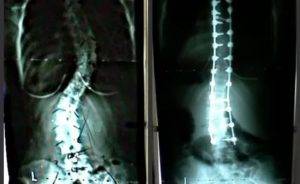

На рентгене данная травма будет отражена в виде тонкой неровной линии на поверхности позвонка.

Это связано с тем, что чаще всего подобные переломы являются компрессионными. Если взглянуть на рентгенографический снимок, то там он будет представлен в качестве трещины в позвонке.